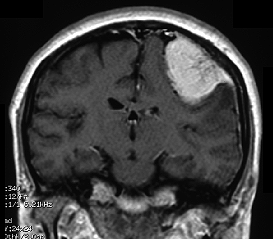

(1) CT、MRI

CT(コンピュータ断層撮影:X線を利用)やMRI(核磁気共鳴影像法:磁気を利用)による脳の断層画像でほとんど診断がつきます。しかし、他にも鑑別しなければならない病気があり最終的な確定診断は手術によって摘出した腫瘍を顕微鏡検査(病理検査)することでなされます。(図-2)